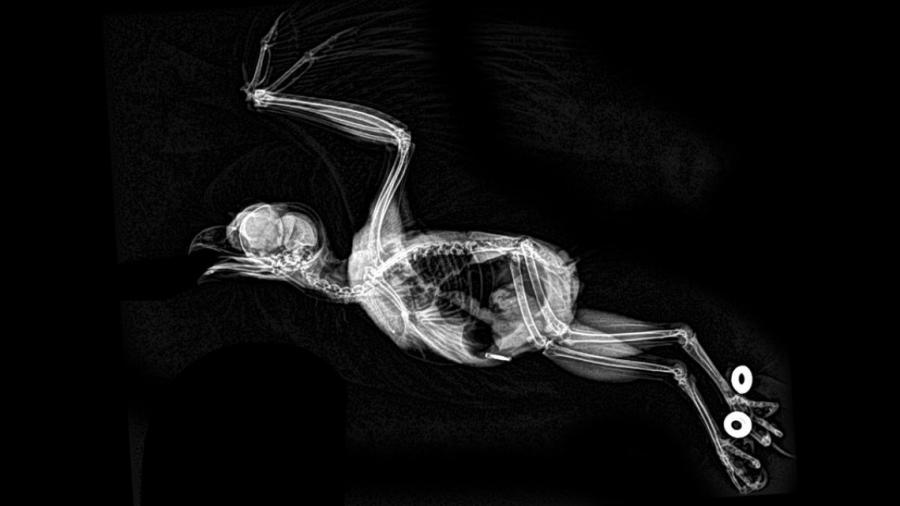

A pocos días de Halloween, el zoológico de Oregón, en Estados Unidos, decidió compartir hace unos días las imágenes hechas en rayos X de sus animales.

Las radiografías fueron hechas durante las inspecciones de salud rutinarias, por lo que en ninguna muestra a un animal enfermo o lastimado.